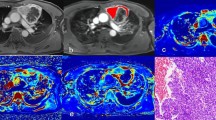

After feature selection, seven texture parameters with good discriminative performance were obtained, including V80 (Cluster Shade_angle90_offset1), V140 (GLCM Entropy_AllDirection_offset3), V153 (Cluster Prominence_AllDirection_offset3_SD), V204 (GLCM Entropy_angle0_offset4), V296 (Cluster Shade_AllDirection_offset6_SD), V312 (Cluster Shade_angle45_offset6), and V735 (Short Run Emphasis_AllDirection_offset5_SD). The statistic results of the ADC and selected texture parameters among LRTs, HRTs, and TCs are shown in Table 3 and Fig. 3.

Box plots for values of ADC (a), V80 (b), V312 (c), and V296 (d) among low-risk thymoma (LRT), high-risk thymoma (HRT), and thymic carcinoma (TC). ADC, apparent diffusion coefficients; V80, Cluster Shade_angle90_offset1; V296, Cluster Shade_AllDirection_offset6_SD; V312, Cluster Shade_angle45_offset6

The mean ADC values in LRTs or HRTs were significantly higher than ones in TC groups according to the one-way ANOVA (ADC, 1.63, 1.30, and 0.86 × 10−3 mm2/s, p = 0.004 and 0.001, respectively), while there were no significant differences in ADC values between the LRT and HRT groups (p > 0.017). With regard to 7 selected DWI texture features, significant differences were found among LRT, HRT, and TC groups (all p < 0.05). After further post hoc multiple comparisons, V80 and V312 values in LRTs were significantly higher than ones in HRT or TC groups (all p < 0.017).

Comparison of ADC values and DWI texture parameters between early and advanced stages of TETs

After feature selection, nine texture parameters with better discriminative performance remained, including V57 (Cluster Prominence_AllDirection_offset1_SD), V204 (GLCM Entropy_angle0_offset4), V278 (Correlation_angle135_offset5), V296 (Cluster Shade_AllDirection_offset6_SD), V735 (Short Run Emphasis_AllDirection_offset5_SD), V920 (High Gray-Level Run Emphasis_AllDirection_offset8_SD), V1025 (Sphericity), V1030 (Maximum 3D Diameter), and V1033 (Spherical Disproportion). The statistic results of the ADC and selected texture parameters between early and advanced TETs are shown in Table 4 and Fig. 4.

The mean ADC value in early-stage TETs was significantly higher than that in advanced-stage TETs (1.48 vs. 1.00 × 10−3 mm2/s, p < 0.001). As for the nine selected DWI texture parameters, significant differences were found between early and advanced stages of TETs (all p < 0.05).

The various parameters derived from imaging texture analysis are biologically regarded as good indices of tumor heterogeneity, which were thought to result from regional differences in tumor cellularity, proliferation, angiogenesis, hypoxia, and necrosis, all of which are related to tumor risk grades [35, 36]. Two recent studies differentiated the pathological subtypes of TETs using PET/CT textural features and demonstrated its potential value in TET tumor grades [27, 35]. In this study, the results showed that several DWI texture parameters were significantly different among various subtypes or stages of TETs. Both V80 and V312 of cluster shade parameters measured the skewness and uniformity of the GLCM (gray-level co-occurrence matrix); a higher cluster shade implied greater tumor asymmetry or less homogeneity. Interestingly, according to our results, V80 and V312 values were significantly higher in LRT than those in HRT or TC, indicating lower tumor homogeneity in LRT, which was out of our expectation. In most cases, malignant tumors have higher tumor heterogeneity due to more necrotic and heterogeneous growth than benign or low-grade malignancies. However, macroscopic appearance of multiple nodules separated by fibrous bands was demonstrated in LRT especially in over 77% of type AB thymomas, and the typical growth pattern is less in HRT and none in TC [11], which might explain why the significant higher V80 and V312 values exist in LRT. In addition, V1030 (maximum 3D diameter) values were significantly lower in LRT than those in HRT or TC in the current study, which were consistent with previous results of longer diameter in advanced stages of TETs than in LRT or early stages [19].